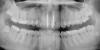

Янa86 Опубликовано 23 октября, 2009 Автор Поделиться Опубликовано 23 октября, 2009 Вот они, мои зубки! Очень хочу получить максимально полную информацию о состоянии моих зубов. Хотелось бы конечно и в перспективе. лет через дцать... Помогите пожалуйста! Извините за настойчивость, просто я очень переживаю! Ссылка на комментарий

Bier Опубликовано 23 октября, 2009 Поделиться Опубликовано 23 октября, 2009 с единичками все прекрасно.похоже есть проблемы с 46з (шестерка внизу справа, на снимке слева)на периодонтит похоже. Перелечивать надо. ну и восьмерки надо удалять. Ссылка на комментарий

Андрей Опубликовано 23 октября, 2009 Поделиться Опубликовано 23 октября, 2009 Вот они, мои зубки! Очень хочу получить максимально полную информацию о состоянии моих зубов. Хотелось бы конечно и в перспективе. лет через дцать... Помогите пожалуйста! Извините за настойчивость, просто я очень переживаю!Нормальные коронки, спите спокойно. Рекомендую поставить коронку на нижний депульпированый зуб и удалить нижнюю восьмерку с той же стороны. Возможно, на левем верхнем боковом резце есть кариес. Ссылка на комментарий

zybnaya feya Опубликовано 23 октября, 2009 Поделиться Опубликовано 23 октября, 2009 (изменено) Вот они, мои зубки! Яна,я так редко говорю эту фразу,но У ВАС ВСЕ ЗАМЕЧАТЕЛЬНО ,даже лучше,чем вот эти смайлы. Все каналы пролечены на пятерочку,как в резцах,так и в 6-ке нижней. Космопосты тоже стоят достаточно глубоки и четко. Не переживайте и радуйтесь жизни. В ней столько приятного)) Изменено 23 октября, 2009 пользователем zybnaya feya Ссылка на комментарий

Bier Опубликовано 23 октября, 2009 Поделиться Опубликовано 23 октября, 2009 Все каналы пролечены на пятерочку,как в резцах,так и в 6-ке нижней.на мой взгляд на медиальном корне 46 зуба явные периапикальные изменения. Ссылка на комментарий

Янa86 Опубликовано 24 октября, 2009 Автор Поделиться Опубликовано 24 октября, 2009 (изменено) Огромное всем СПАСИБО, чтобы я без вас делала, столько высококлассных специалистов уделили мне внимание . Прямо бальзам на душу от ваших сообщений! По снимку все подметили: 1. На корнях шестерки снизу есть какие-то образования, уже перелечила около месяца назад (перепломбировали канала), возможно ткани еще не успели восстановится. Коронку наверное рано ставить, врач пока не предлагал. 2. На левом резце действительно кариес в виде пятна, стоматолог сказала, что сверлить рано, а ничего другого не предложила. Где-то на форуме прочитала, что можно это место подшлифовать, поможет? 3. По поводу восьмерок: хирург говорит удалять; ортопед – грозит воспалением, но можно и подождать; стоматолог – советует не спешить, удалить всегда успею, если начнут беспокоить. Так что я пока в растерянности. Fury, я себе наверное мотоциклистский шлем куплю Кстати, я на передние зубы теперь практически не даю нагрузку, это тоже ведь не очень хорошо для десен? Еще беспокоит вопрос по поводу старения вкладки, она ведь не рассыплется под коронками через лет 50, по крайней мере, не должна? Очень хочется встретить старость с передними зубками . В дальнейшем планирую поставить ДЦ коронки, это ведь возмонно на космопост? Изменено 24 октября, 2009 пользователем Янa86 Ссылка на комментарий